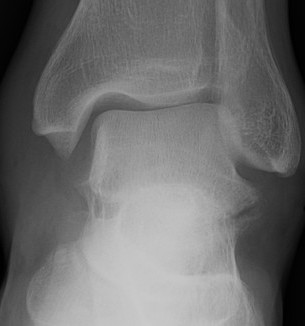

X-ray

Best seen on mortise view